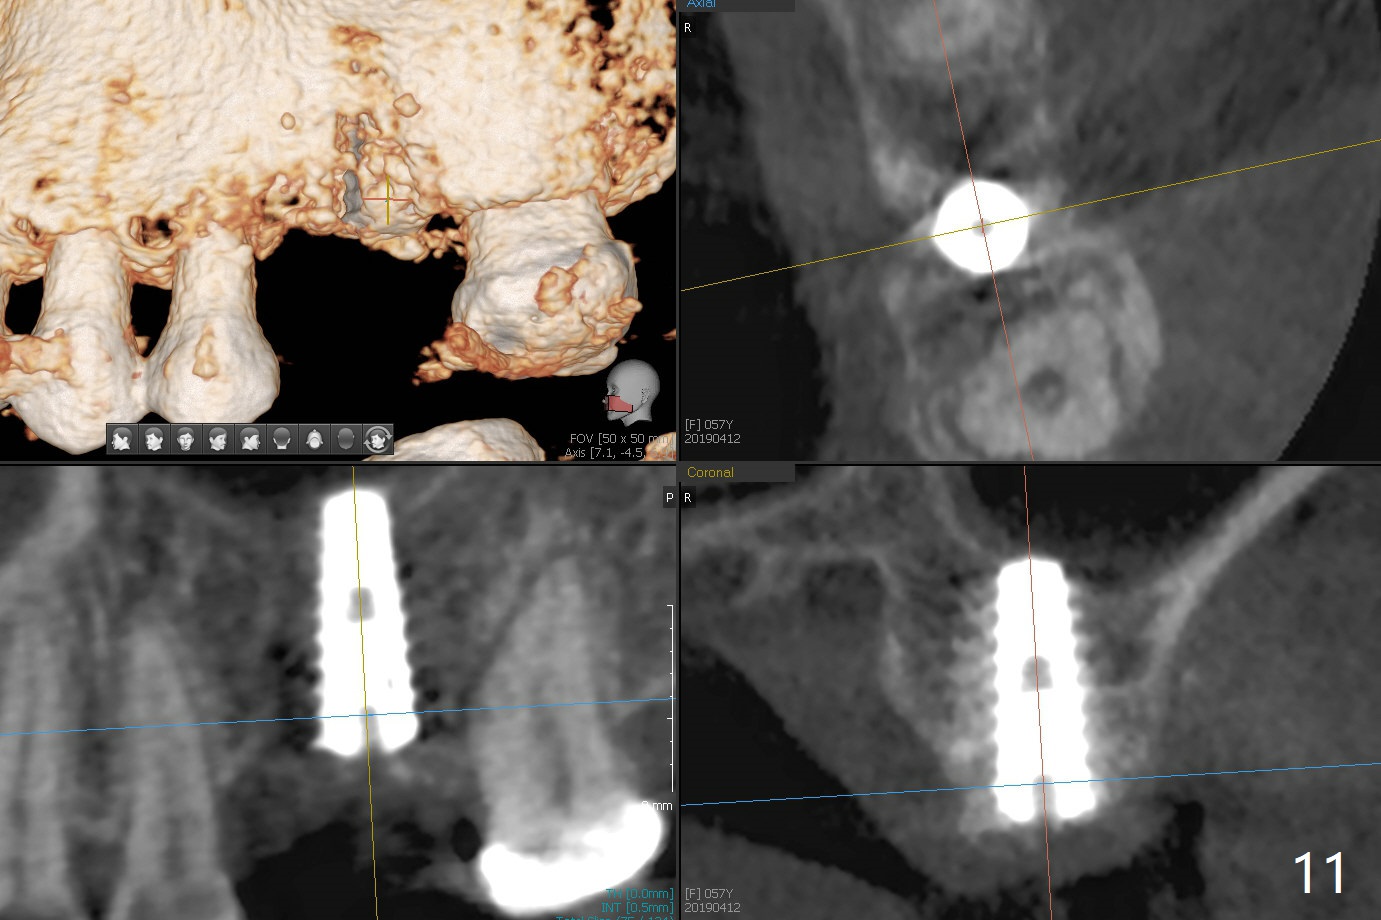

A 57-year-old woman complains of bad smell while use of water flosser between 11 and 21 months post cementation of implant crown at #14 (Fig.1,2). Bone loss is more obvious with CBCT (Fig.3,4), in spite of apparently normal gingiva around the implant after removal of the abutment and crown (Fig.5). In fact the buccal (B) gingiva is fragile with easy access to the underlying implant plateau. Following flap elevation, the bone loss is evident (Fig.6), but the implant plateau is slightly subcrestal (Fig.7 *). The exposed implant threads are covered with the 1st round of bone graft (Fig.8). After 2nd round of allograft (Fig.10-12) and collagen membrane, the flaps are approximated (Fig.9). The wound is covered by acrylic dressing. The latter is loose, but stays in place 1 week postop (Fig.13). Due to short neighboring teeth, the acrylic dressing is able to be removed with wiggling; it appears that the wound is healing (Fig.14). The dressing returns for another 2 weeks; some of the graft has been lost (Fig.15). The dressing does not return 7 weeks postop, since the wound is healing (Fig.16).